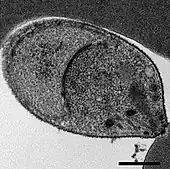

Malaria is traditionally diagnosed by examining Giemsa-stained blood films under a microscope; however, differentiating P. knowlesi from other Plasmodium species in this way is challenging due to their similar appearance.[11] P. knowlesi ring-stage parasites stained with Giemsa resemble P. falciparum ring stages, appearing as a circle with one or two dark dots of chromatin.[18] Older trophozoites appear more dispersed, forming a rectangular-shape spread across the host cell called a "band-form" that resembles the similar stage in P. malariae.[18] During this stage, dots sometimes appear across the host red blood cell, called "Sinton and Mulligans' stippling".[18] Schizonts appear, similarly to other Plasmodium species, as clusters of purple merozoites surrounding a central dark-colored pigment.[18]